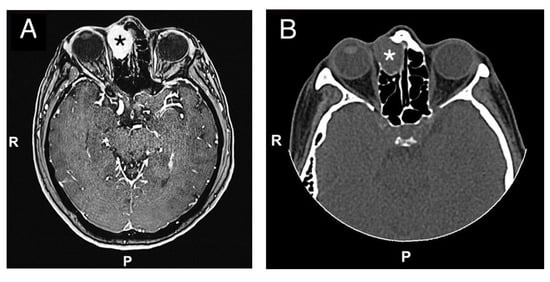

Figure 1.

(A) Preoperative MRI (Time Of Flight TOF sequence in axial view; black asterisk) and CT-scan (B) (axial view; white asterisk) (C) (coronal view; white asterisk), (D) (sagittal view; white asterisk) showing an anterior ethmoidal high vascularized tumor invading the right nasal bone and the medial wall of the right orbit. R = right, P = posterior.